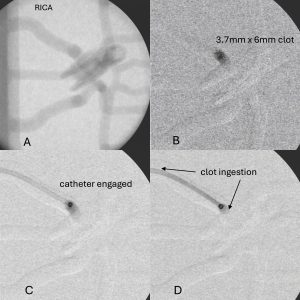

- The radiopaque synthetic clots contain barium-sulfate for visualization via angiography to provide clinically relevant in vitro visualization of the clot during full benchtop surgical simulations.

- Reproduceable “soft” and “hard” clots are formulated to be visible via PIV and angiography imaging.

- BDL synthetic clots are composed of polyacrylamide and alginate and are compatible with particle image velocity (PIV) and radiographic imaging techniques